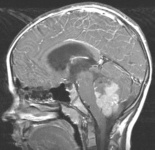

Meduloblastoma: vista sagital de ressonância nuclear magnética (RNM) mostrando uma lesão sólida e cística com ávido realce ao contraste que preenche o quarto ventrículo; presença de hidrocefalia obstrutiva

Do acervo de Peter B. Storm; usado com permissão